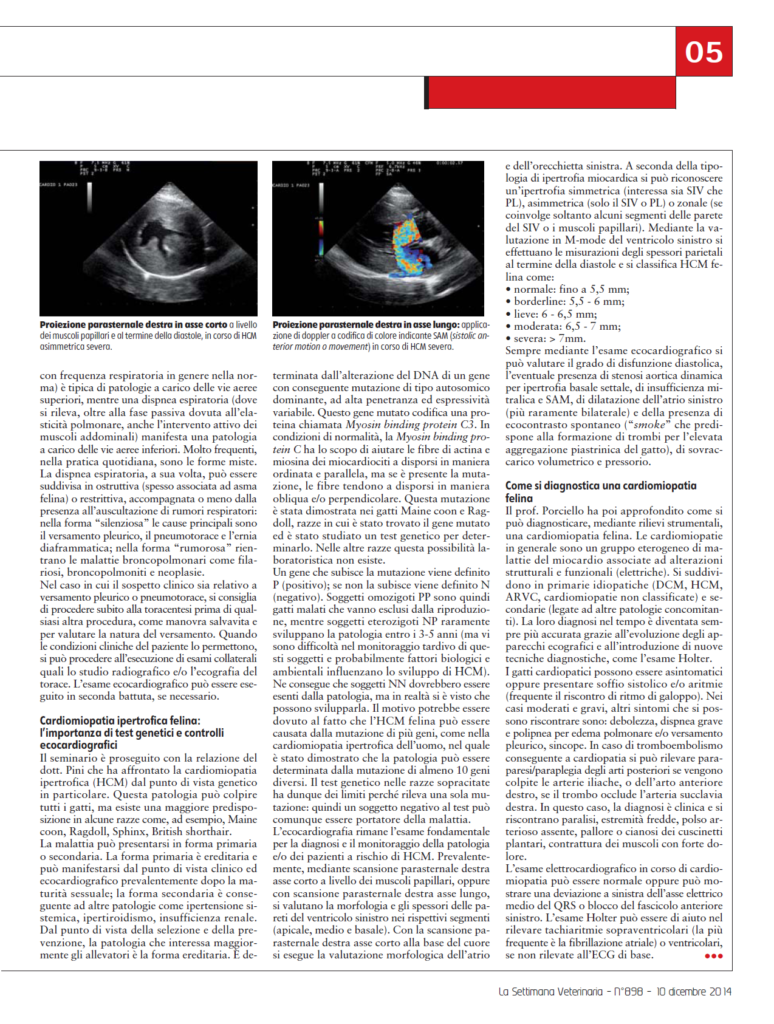

Prevalentemente mediante scansione parasternale destra asse corto, a livello dei muscoli papillari, oppure con scansione parasternale destra asse lungo, si valuta la morfologia e gli spessori delle pareti del ventricolo sinistro nei rispettivi segmenti apicale, medio e basale).

Sempre mediante l’esame ecocardiografico si può valutare il grado di disfunzione diastolica, l’eventuale presenza di stenosi aortica dinamica per ipertrofia basale settale, di insufficienza mitralica e SAM, di dilatazione dell’atrio sinistro (più raramente bilaterale) e della presenza di eco contrasto spontaneo (“smoke” che predispone alla formazione di trombi per l’elevata aggregazione piastrinica del gatto), di sovraccarico volumetrico e pressorio.